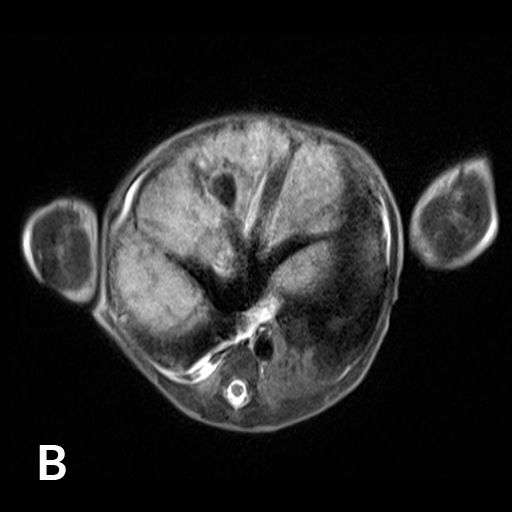

Ausgedehntes fokales Leberhämangiom eines Neugeborenen

Reifes Neugeborenes mit Hepatomegalie und Herzinsuffizienz. Das MRT der Leber (A) zeigte ein ausgedehntes kongenitales Hämangiom mit normalem Lebergewebe in den Randbereichen vor allem links. Deutlich gestaute Lebervenen (B) infolge der Rechtsherzbelastung. Die Kontrastmittelinjektion die Arteria hepatica dextra (C) zeigt mehrere arterielle Feeder mit rascher Parenchympassage. Nach interventionellem Verschluss mittels 3 Vascular Plugs und insgesamt 28 Volumen-Coils deutliche Reduktion des Shunt-Flusses im rechten Leberlappen mit noch verbleibenden Hämangiomanteilen links (D).